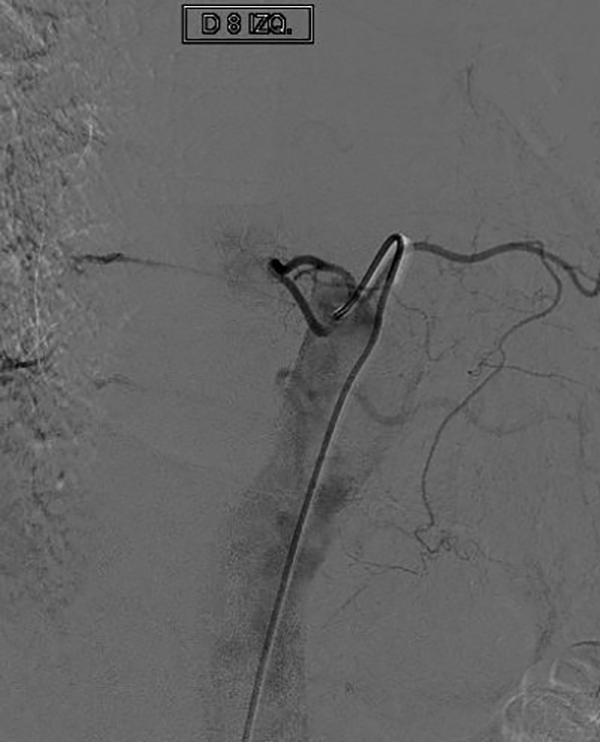

CASO #1. Paciente masculino de 52 años con una historia de 6 meses de evolución de disestesias en ambos miembros inferiores, inestabilidad en la marcha, hiperreflexia y urgencia miccional. Se estudió con RMN (Fig. 3), ARM (Fig. 4) y ADM seguida de embolización con oclusión total de una FDAVE D8 izq. (Fig. 5). Evolucionó sin déficit y a los 11 meses comenzó con la misma sintomatología previa a la embolización. Se estudió nuevamente y la ADM (Fig. 6) mostraba la recidiva de la FDAVE y fue derivada para microcirugía (Fig. 7). Luego de la cirugía evolucionó sin déficit, se realizó una ADM diferida (Fig. 8) y lleva 116 meses libres de enfermedad.

Figura 5: Caso #1. ADM mostrando la FDAVE en D8 izq. antes y después de la embolización. En la imagen de la izquierda (pre-embolización) las flechas blancas muestran la vena de drenaje de la FDAVE desde el punto fistuloso (más lateral) hacia medial en forma descendente y llegando a la línea media en donde se anastomosa con la vena espinal posterior y continúa hacia abajo en forma serpiginosa. La foto de la derecha (post-embolización) dejó de observarse la vena de drenaje y la vena espinal posterior (oclusión total de la FDAVE).

Figura 6: Caso #1. FDAVE recanalizada a los 15 meses post-embolización. ADM de frente (izquierda) y de perfil (derecha) las flechas blancas muestran el trayecto ascendente de la vena de drenaje. En el perfil se observa además que la vena de drenaje es dorsal.

Figura 8: Caso #1. ADM postoperatoria alejada que demuestra la ausencia de la FDAVE en D8 izq.